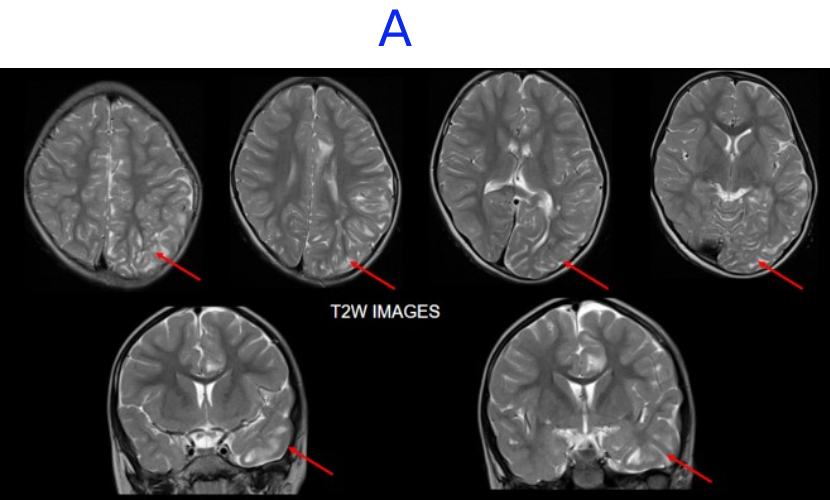

A. FINDINGS: MRI BRAIN WITH IV CONTRAST

• A. There is hemihemimegelencephaly in the left parieto-temporo-occipital lobes, characterized by enlargement of the involved hemisphere. There is associated gyral thickening with white matter signal changes in the adjacent subcortical white matter.

• B. Areas of rarefaction are seen in white matter signal changes. Note is also made of periventricular nodular heterotropia along the atrium of the left lateral ventricle.

Left posterior quadrantic dysplasia with associated subcortical white matter signal abnormalities and periventricular nodular heterotropia.